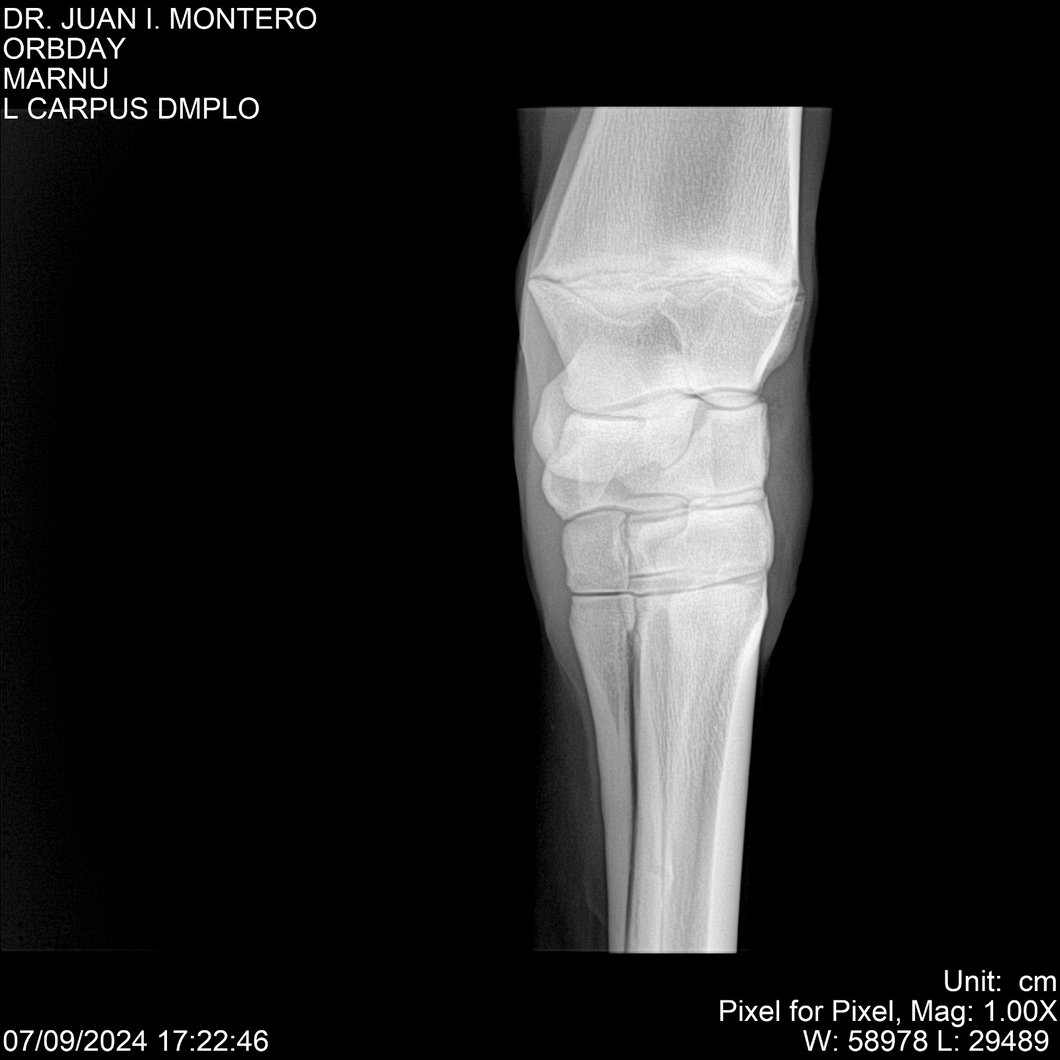

Visualizaciones